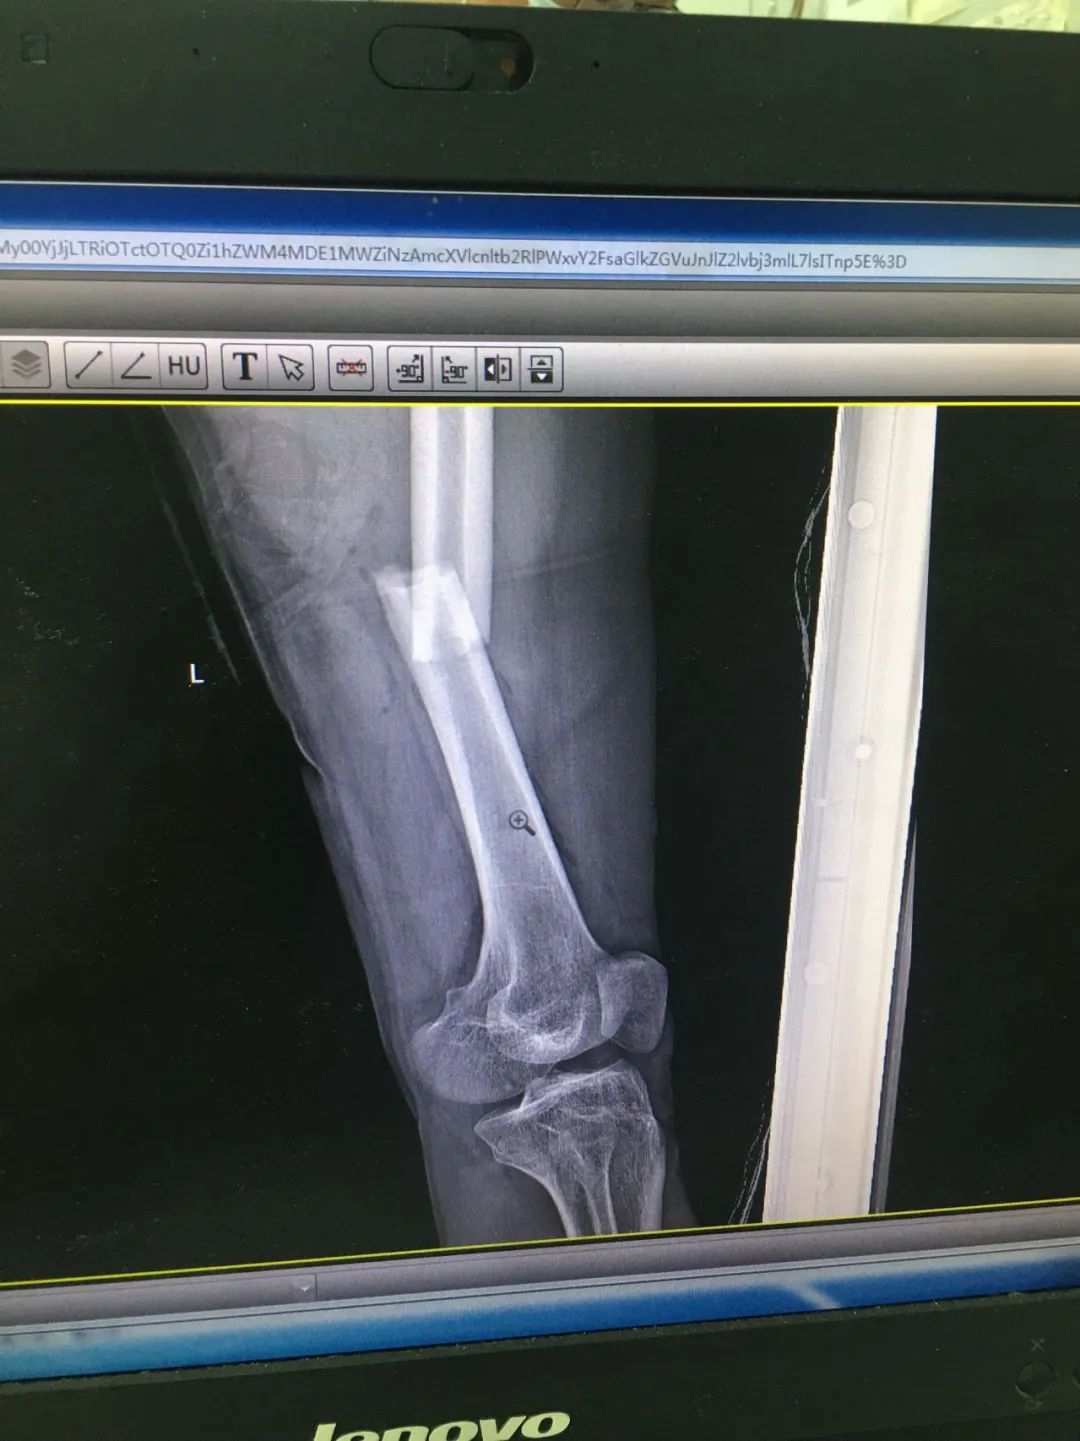

第1次手術(shù)10天后,骨科為劉先生安排了第2次手術(shù),歷經(jīng)3個(gè)小時(shí),成功完成左股骨干骨折及左脛骨遠(yuǎn)端骨折閉合復(fù)位內(nèi)固定術(shù),植入兩根30cm×10mm、34cm×10mm髓內(nèi)釘。

術(shù)后一周,患者手術(shù)切口愈合良好,左下肢皮膚感覺及肌力正常,左足末梢循環(huán)恢復(fù),復(fù)查X片顯示骨折復(fù)位標(biāo)準(zhǔn),內(nèi)固定物位置良好。